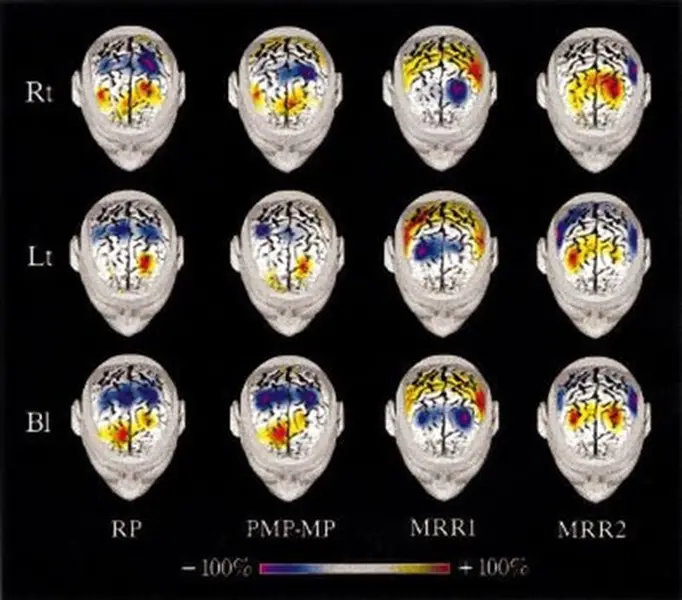

Risposte delle Aree Sensori-Motorie Primarie e dell’Area Motoria Supplementare Umana a Movimenti Unilaterali e Bilaterali Autoindotti: uno Studio EEG ad Alta Risoluzione

Lo studio utilizza l’EEG ad alta risoluzione per analizzare le aree motorie del cervello durante movimenti unilaterali e bilaterali, mostrando una maggiore attivazione dell’emisfero sinistro durante la pianificazione e l’esecuzione dei movimenti.